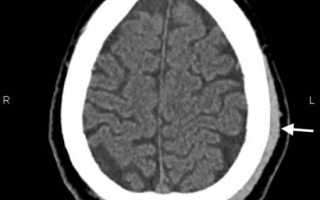

КТ головного мозга: гематома периферических мягких тканей левой теменной области.

image